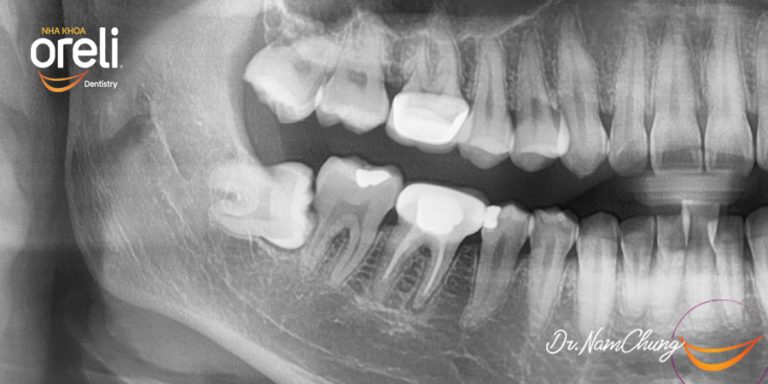

Nhổ răng khôn hàm dưới – Case tại Oreli Buôn Ma Thuột

Nhổ răng khôn

Mọc lệch